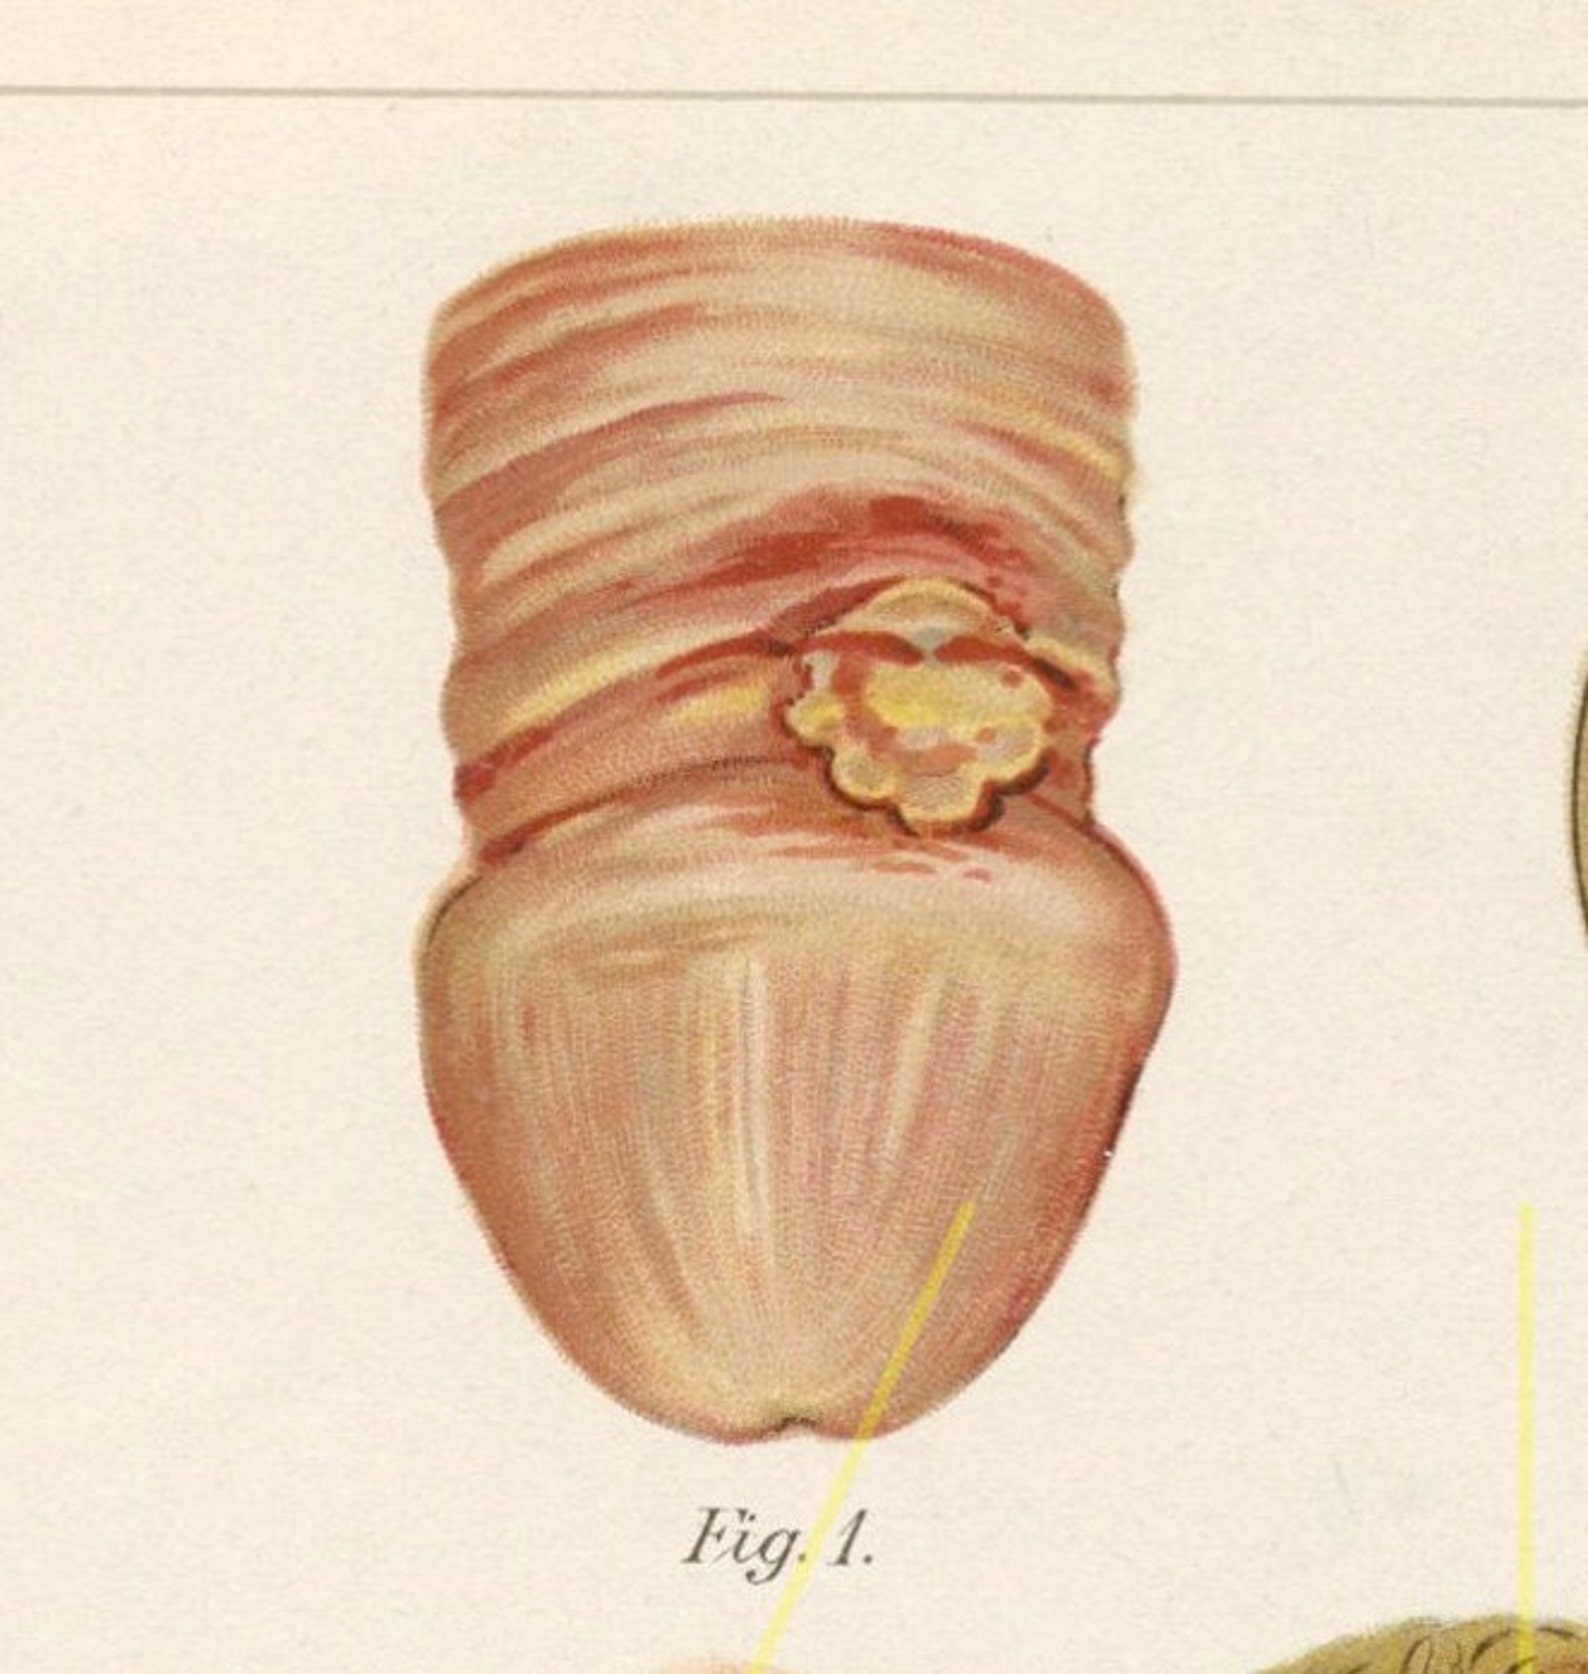

Photograph from ‘Atlas of Syphilis and the Venereal Diseases’ , 1898 …

Antique syphilis print. Medical illustration. STD. Chancre. | Etsy

This image is taken from Atlas of syphilis and the venerea… | Flickr